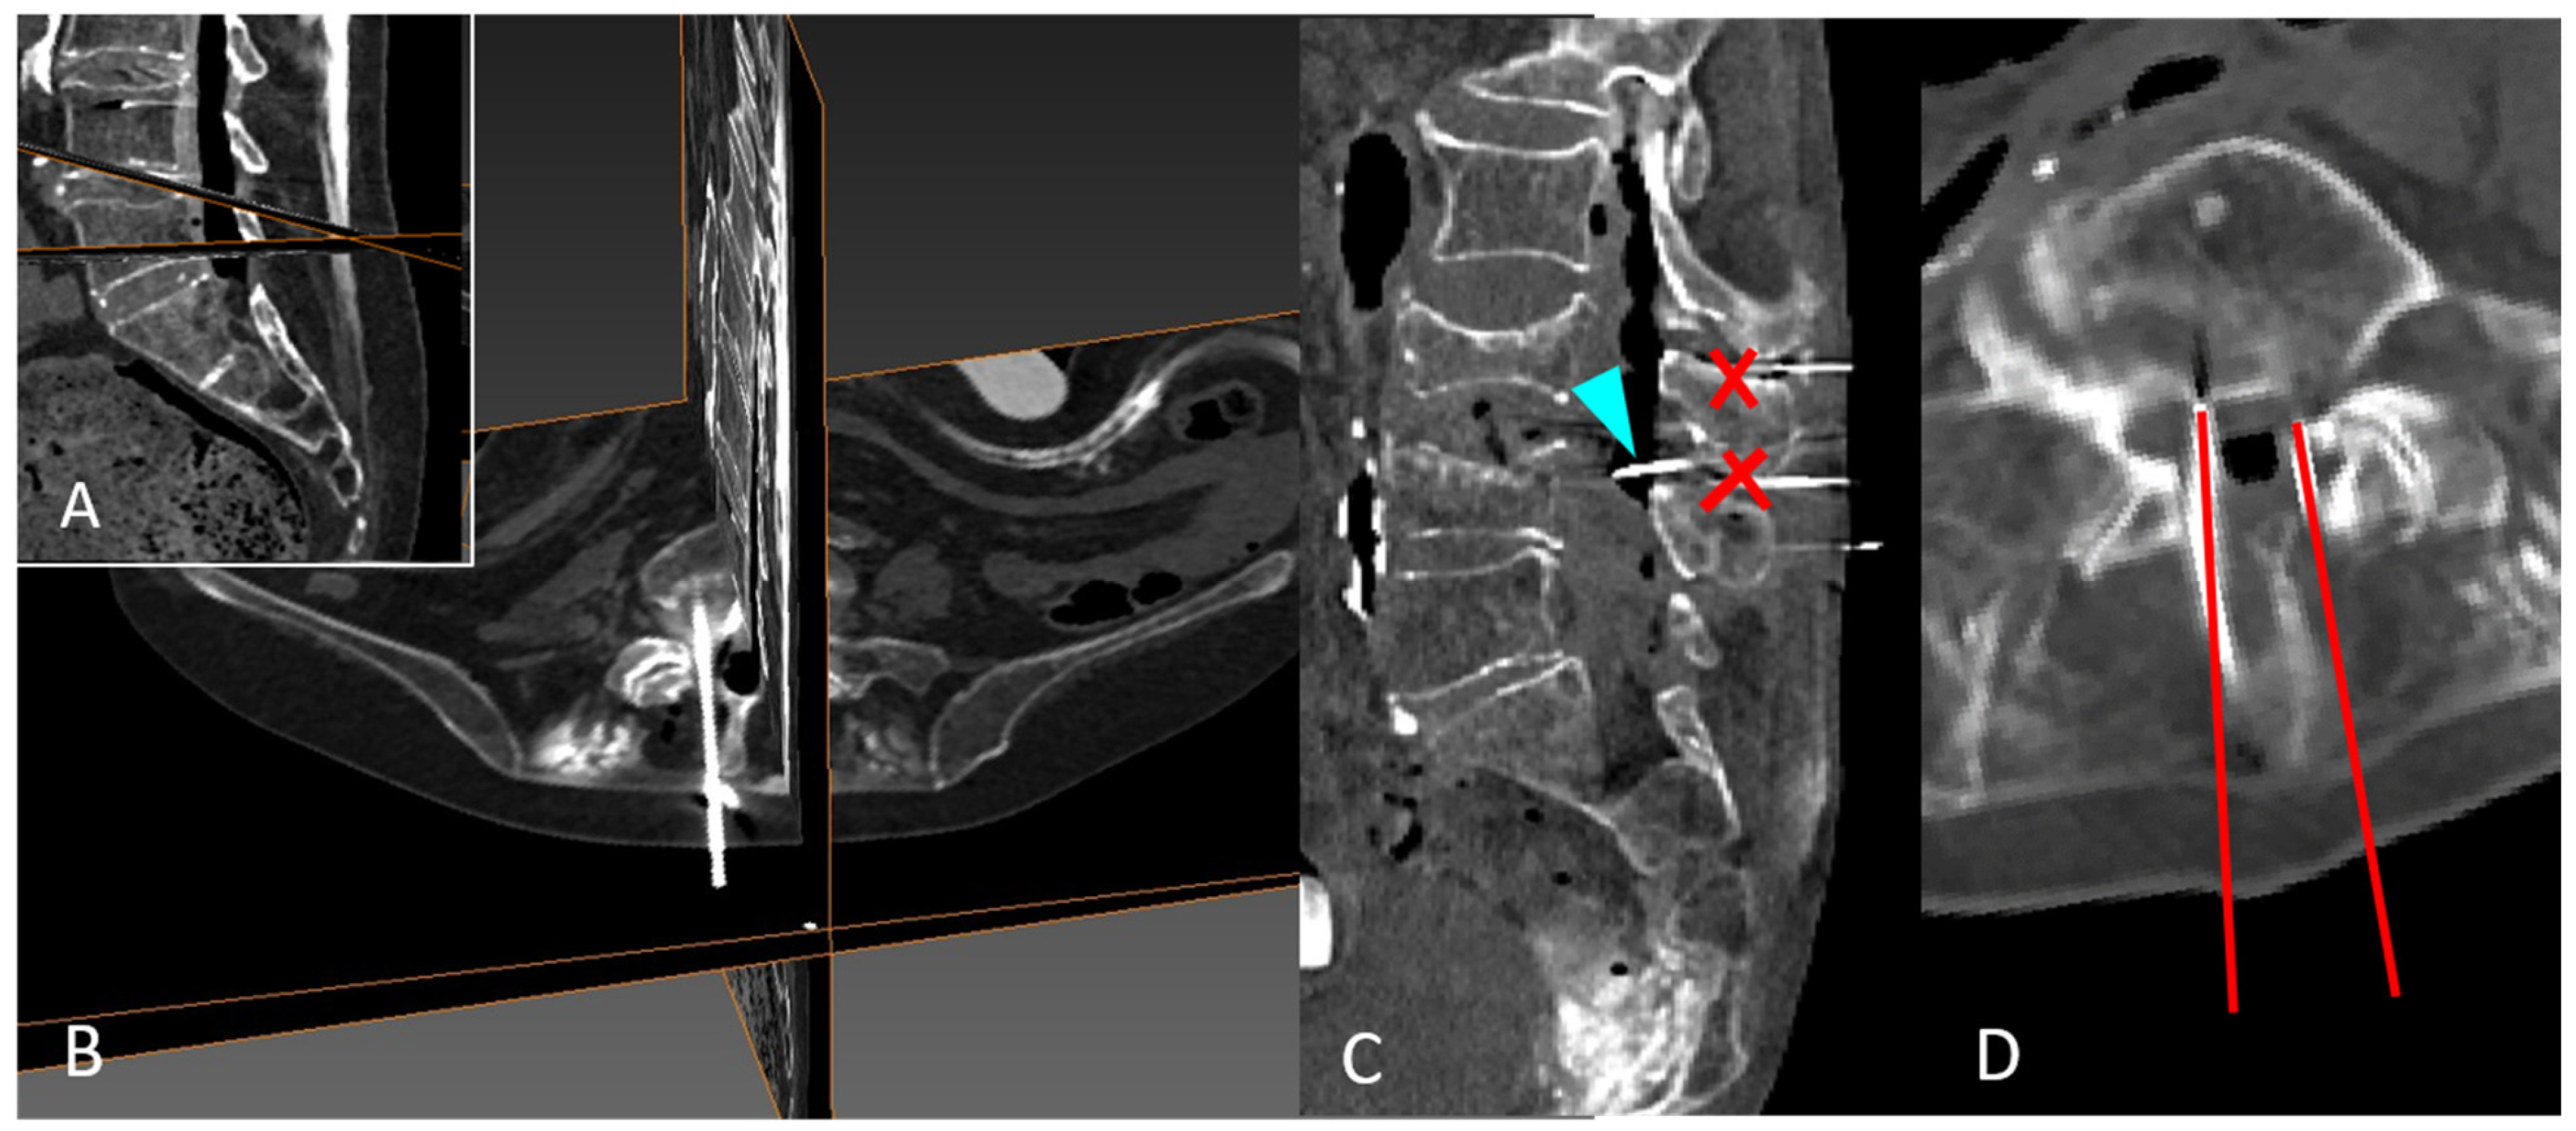

2.5. CT and 3D Reconstruction

2.6. Anatomical Illustration of Needle Path and Affected Structures

3. Results